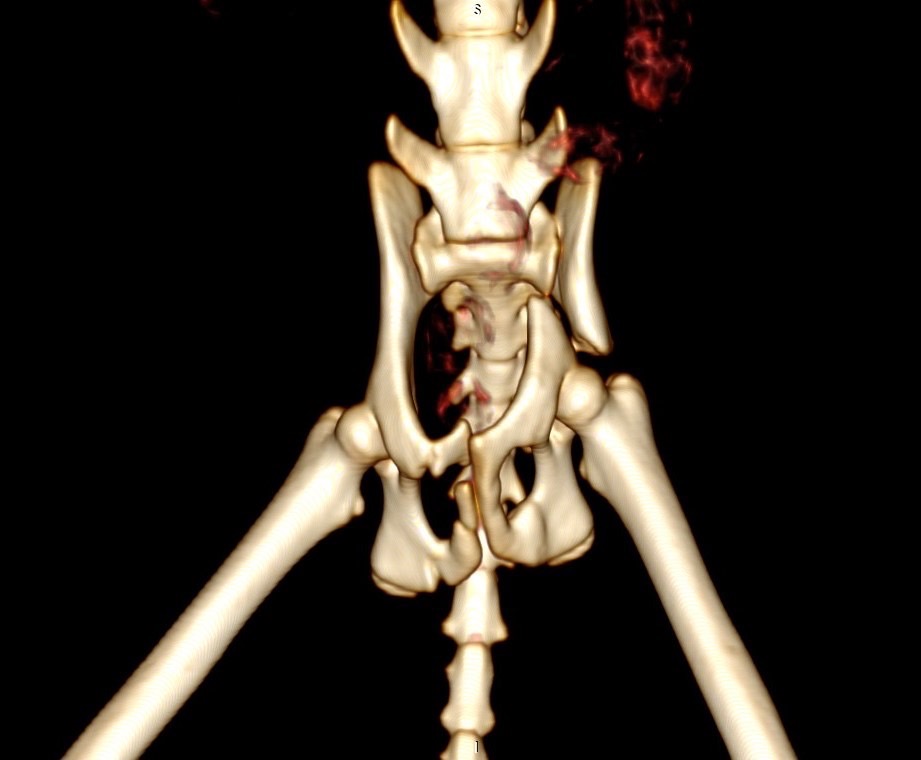

狗狗 車禍 骨盆骨折

狗狗的骨盆骨折相對於常見的四肢骨折 不容易單純靠xray 診斷及擬定手術計畫藉由電腦斷層影像的支援 能提高手術成功的機率

14kg 11歲的莓莓 術後10個月追蹤 行動自如一切正常喔

術前

術後

電腦斷層影像